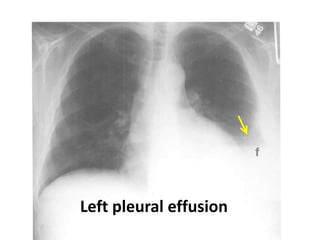

Left pleural effusion

Pleural effusion